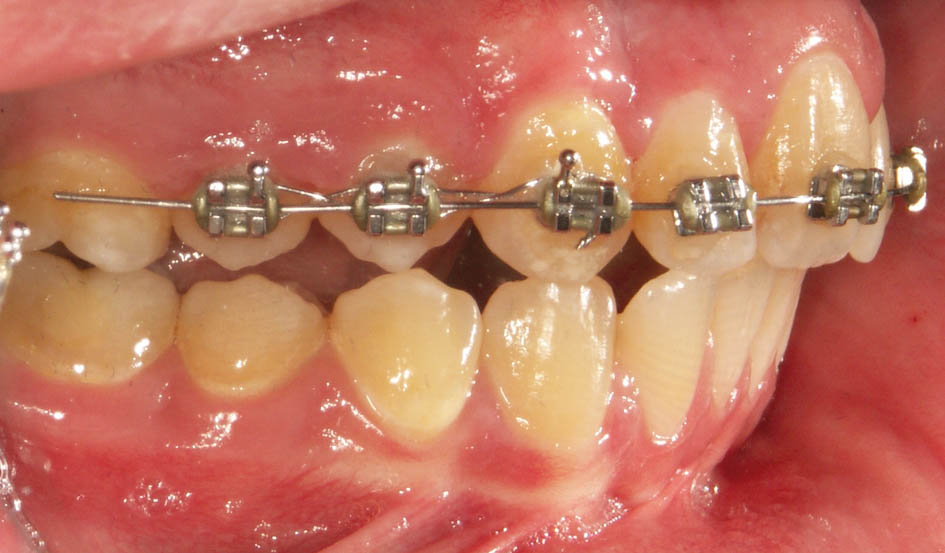

گاهی بیمار شما Div2 است و بخاطر رترودشدن انسیزورهای بالا و دیپبایت شدن بیمار دیگر اورجت ندارید. بیمار مندیبل را در زمان تهیه موم باید جلو بیاورد و چون اورجت ندارید این کار عملی نیست، لذا باید ابتدا اورجت بسازید و بعد موم بایت بگیرید (شکل 72-5 و 73-5).

شکل 72-5: بیمار کلاسII و دیپ بایت است.

در این مواقع باید دندانهای قدامی را پروترود کنید. میتوانید یک پلاک آکریلی بسازید و Z Spring پشت قدامیها میگذارید یا چند تا براکت با یک سیم 0.012 سوپرالاستیک بگذارید. طبیعی است که گذاشتن چند براکت (شکل 74-5 و 75-5) خیلی سریع و در کمتر از 2 ماه جواب میدهد و نیاز به همکاری از جانب بیمار خیلی کمتر است.

شکل 74-5: چسباندن چند براکت و قراردادن سیم 0.012 سوپر الاستیک برای ساختن اورجت (تبدیل بیمار کلاس II/2 به II/1).